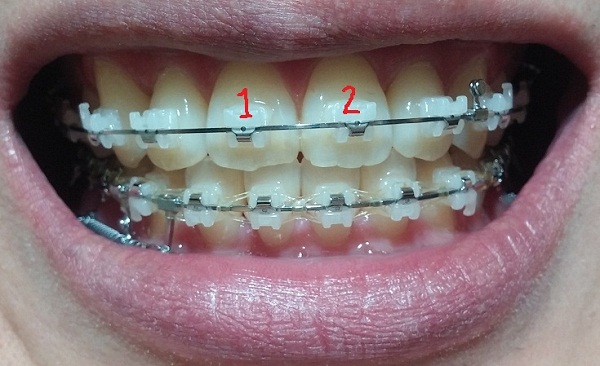

-고무줄착용하기(전 치료와 동일)

-중심선 99% 맞은 상태!!

지금은 다행히 중심선도 다시 맞고 사진을 보시면 아시겠지만 교합이 거의 맞는 듯합니다.

[스프링 정면]

[고무줄 정면]

[고무줄 왼쪽]

[고무줄오른쪽]